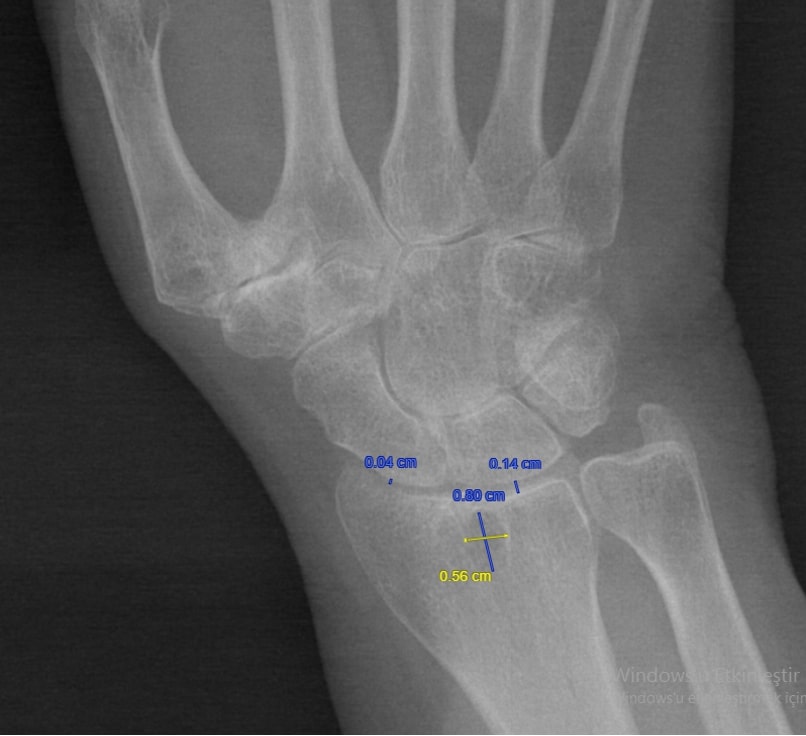

Methods: The HUR-BIO database was established in 2005, 2355 RA patients were registered as of January 2023. Anterior-posterior standard hand X-rays of the first 500 patients in HUR-BIO who had at least one hand X-ray were evaluated. The most recent hand X-ray of the patients was evaluated. From 500 patients in 28 (5.6%) patients, the presence or absence of subchondral cysts on radiographs could not be determined. 24 (4.8%) patients had cystic-erosive changes in the radius, but these patients were not included in the analysis because the bone integrity of the radius cortex was compromised. The localisation and size of the geodes, the distance from the distal part of the radius, the distance from the geodes to the radius, and the distance between the radius and the carpal bone were measured.. The distance between the radius and scaphoid and the distance between the radius and lunate bone were measured at the narrowest point (Figure 1). Involvement of the carpal bones was evaluated according to the modified Larsen score. Demographic, clinic characteristtics were assessed and compared between patients with and without goedes.

Results: Goedes were found in 63/448(14.1%) of these patients. Mean (SD) years of age at the time of hand x-ray was 54.4 (12.4) and 51.1 (12.9) in with/out goedes, respectively In the comparison of patients with/out goedes, there were differences in terms of male gender and anti-CCP positivity and disease duration. Larsen score in carpal bones was worse in patients with subchondral cysts (Table 1). A total of 98 cysts were found in 63 patients; 8 (12.6%) unilateral single cyst 37 (58.7%), unilateral double cyst 14 (22.2%), bilateral 12 (19.0%). The dominant cyst on the right was found in 40 patients and the second cyst in 14 patients, while the dominant cyst on the left was found in 35 patients and the second cyst in 9 patients. The distribution of sclerosis around these cysts was as follows; absent 4 (4.1%), mild 59 (60.2%), moderate 33 (33.7%), marked 2 (2.0%). The mean (SD) distance between the upper end of the cyst and the radius was 1.7 (0.67) mm. In 26 patients with multiple cysts, anti-CCP antibody positivity was more frequent (90.0% vs 64.3%, p=0.043), and Larsen score of grade 2 or higher was more frequent (92.3% vs 67.6%, p=0.020) Patients with subchondral cysts larger than 50 mm2 were more frequently male (64.7% vs 21.7%, p=0.001), smoking was more frequent (76.5% vs 43.2%, p=0.020).(Table 2).